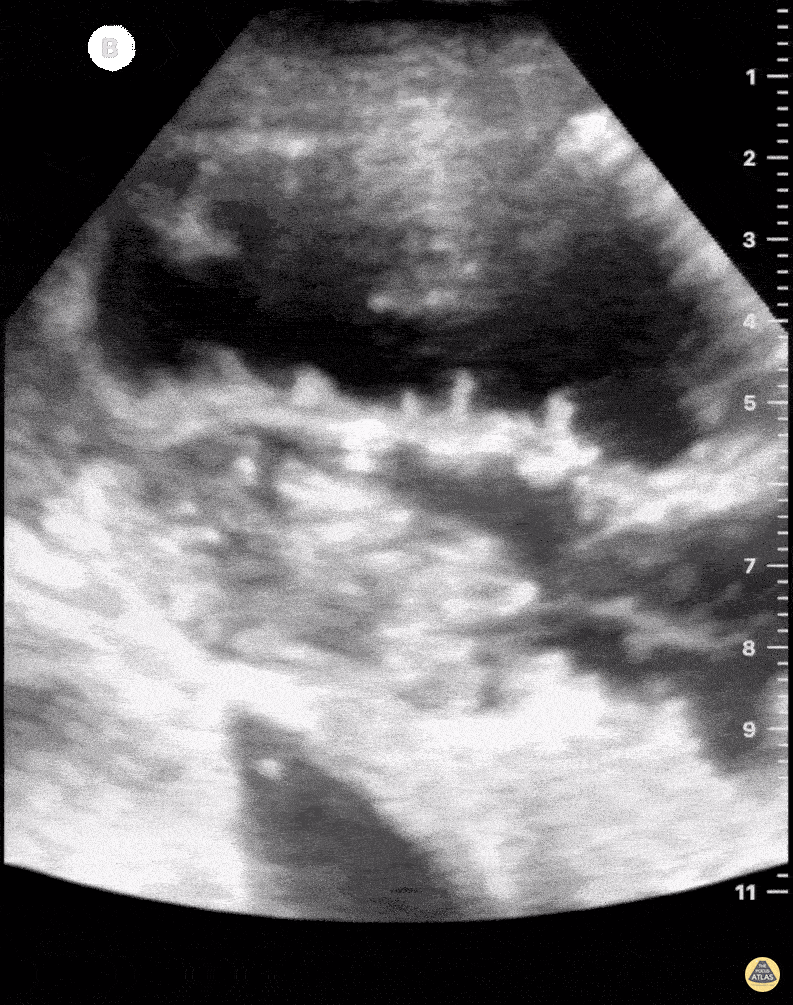

Sign of small bowel obstruction. We see heterogeneous material inside the loop of bowel with a back and forth movement, characterizing the obstruction. The patient in question had a paralytic ileus due to chronic antipsychotic use. Felipe Teles; Internal Medicine at Fortaleza General Hospital @drfelipemoraisteles